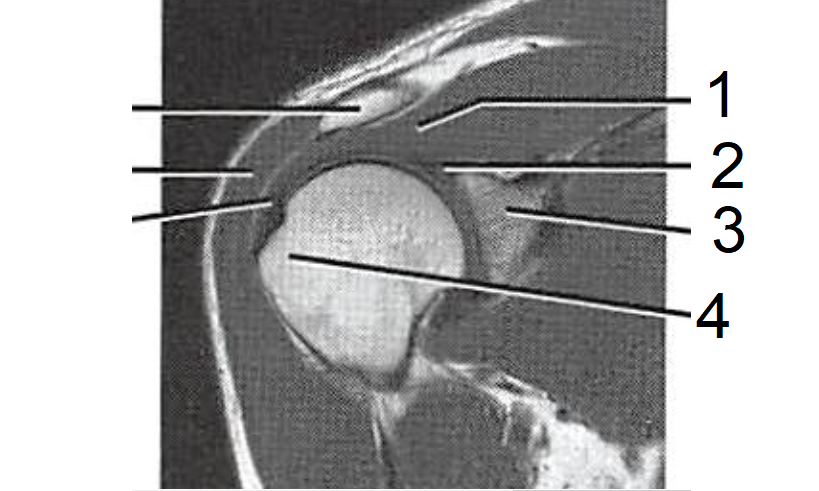

1 - Tendão do M. supraepinhal

2 - M. deltoide

3 - Ligamento glenoumeral